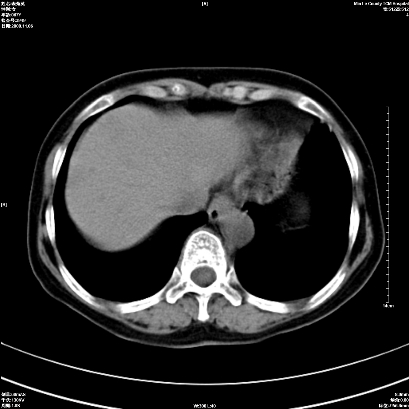

以下是引用卜一在2008-11-6 15:58:00的发言:[br]胰头略增大,胆总管扩张,末端渐行性狭窄。多考虑:胰头癌!建议增强!